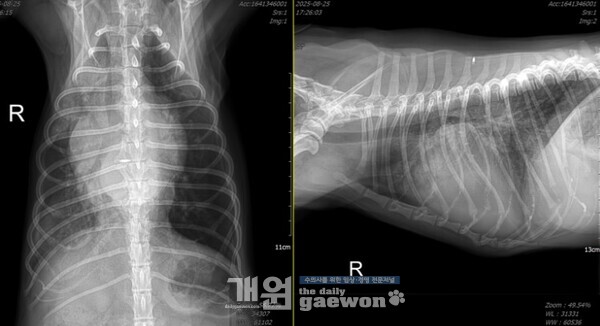

또 다른 환자의 흉부방사선이다.

이 환자는 2년간 피모벤단을 먹으면서 B2 로 관리받았고, 최근에 한 번의 폐수종이 있었는데, 그 이후로 퇴원이 안 되는 상황이었고, 고려 응급실로 밀고들어와서 투석부터 하고있다. 이뇨제는 신장수치때문에 더 쓸 수가 없고, 투석의 초여과 기능을 통해 폐의 물을 뺐다.

폐수종이 터졌냐 안터졌냐 가 기준이 아니라, 심장의 기능과 판막륜의 변형력이 충분히 남아있을 때 수술을 하면 좋은 예후를 얻을 수 있다.

심장병 얘기 들은적도 없는데 갑자기 폐수종부터 왔던 환자들이, 심지어 그 환자들이 D 단계로 직행했는데도 불구하고 클램프 수술 후 이뇨제 끊고 강심제도 끊을 수 있는 것은, 다 변형력이 좋고 심장의 기능도 좋고, 심장병을 앓은 시간이 오래되지 않아서 일 것이다.